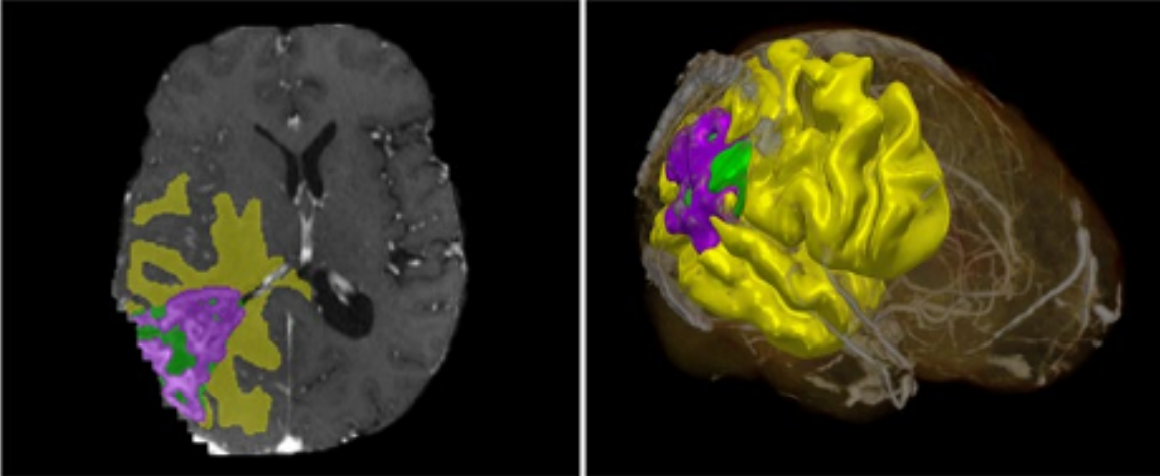

«Il termine tecnico è segmentazione, un processo che permette di delineare il profilo di un determinato oggetto in un’immagine 2D, per produrne una ricostruzione in 3D».

In campo medico, consiste nell’unire varie fotografie ottenute da radiografie o TAC, e identificare con un tratto colorato l’organo o la lesione di interesse. Usare dei modelli IA rende più veloce questo processo, ed evita i bias o gli errori umani.